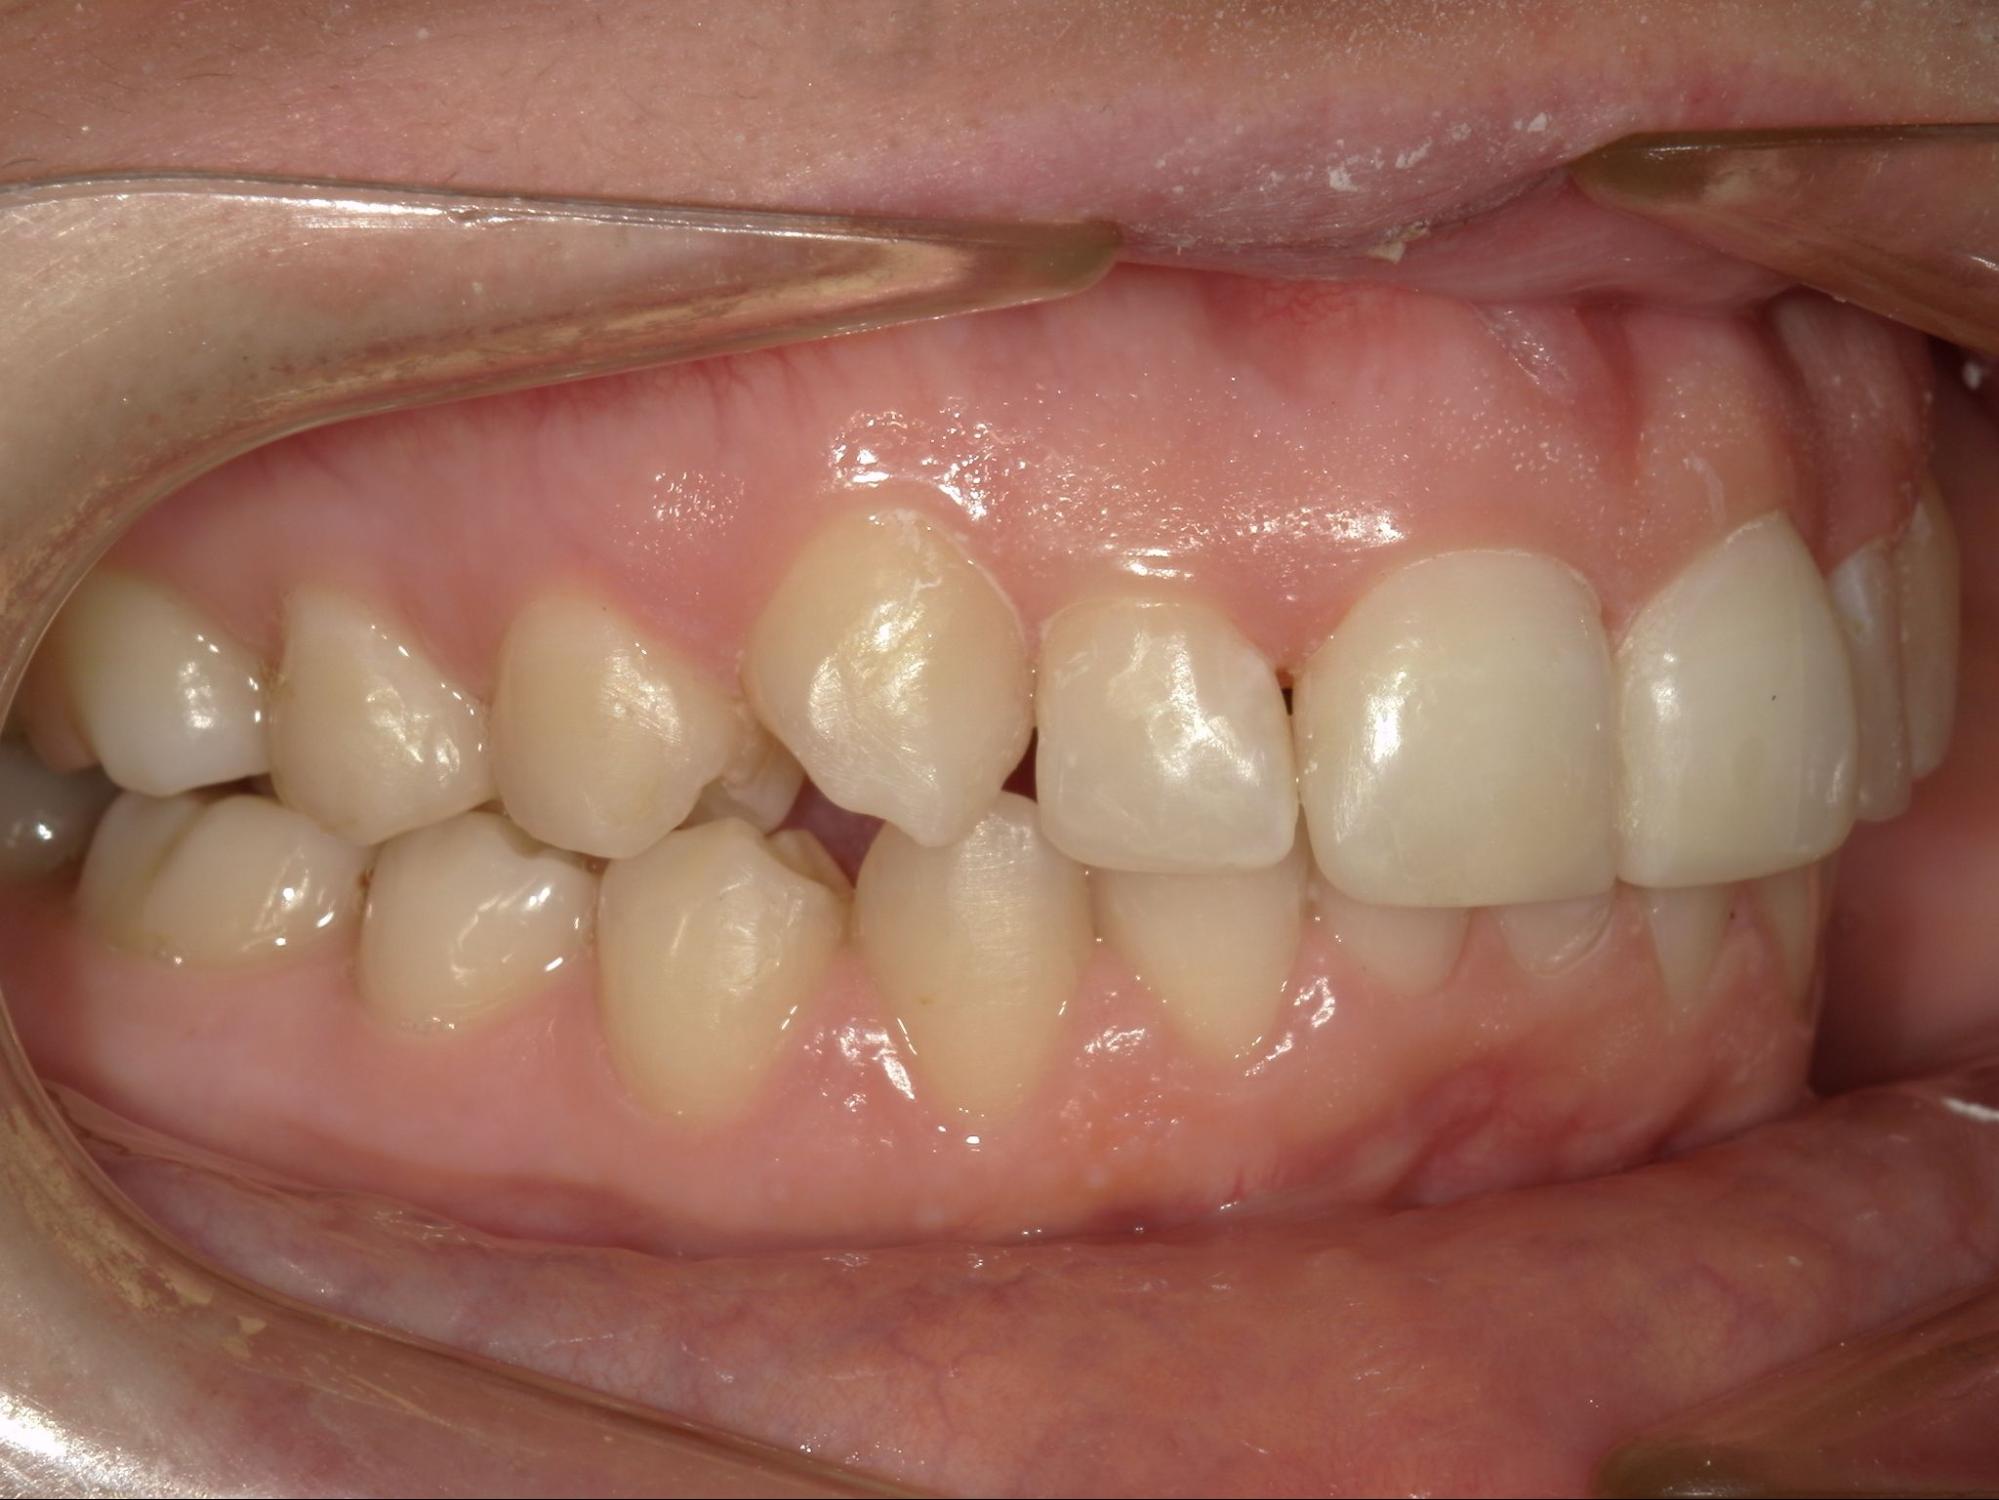

Клинический случай

В практике стоматолога-ортодонта Герасимовой Яны Олеговны есть интересный случай коррекции прикуса на элайнерах. Елена пришла на прием с жалобами на эстетику улыбки, затрудненное открывание рта, пережевывание пищи. Из-за неправильного положения зубов верхние центральные резцы травмировали десны в области нижних зубов, что приводило к частым воспалительным процессам, а также опущению уровня десны. Со временем это привело к формированию повышенной чувствительности зубов — резкой боли при действии холодного, кислого.

При обследовании было выявлено множество проблем. Во-первых, нижняя челюсть имела неправильную форму, была недоразвита. Во-вторых, зубы верхней челюсти занимали неправильное положение, был диагностирован глубокий прикус.

Было принято решение о лечении на элайнерах. После снятия цифровых слепков был составлен план, а Елена увидела, как будет выглядеть ее улыбка еще до начала лечения. Всего было изготовлено 36 капп, которые нужно было носить в течение 22 месяцев. В результате удалось:

• расширить нижнюю и верхнюю челюсть;

• нормализовать положение зубов;

• добиться правильного смыкания зубов;

• изменить в лучшую сторону черты лица, избавиться от второго подбородка;

• уменьшить выраженность носогубных складок;

• улучшить функцию жевания.